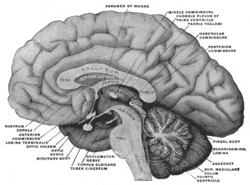

Diagram of the fornix. Right=anterior | |

Fornix of the mouse brain | |

Velum interpositum. Medial aspect of a brain sectioned in the median sagittal plane.

Medial aspect of a brain sectioned in the median sagittal plane. Coronal section of brain through intermediate mass of third ventricle.